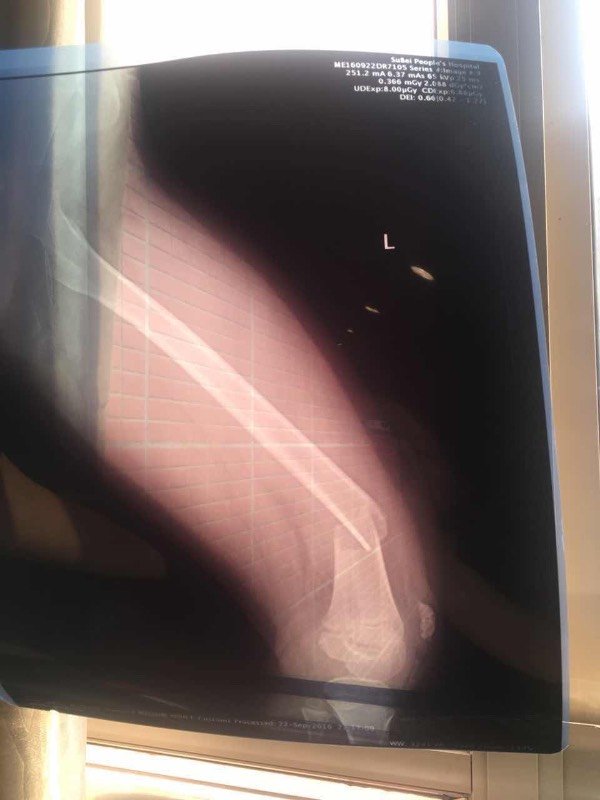

宝宝7岁,左腿股骨骨折,在南京儿童医院住院,医生建议手术治疗,但说因为小孩还会生长发育,因为骨折部位靠近膝盖,所以后期腿可能会长歪,也找人咨询过其他专家,有的说手术是首选,但也可以先试试看保守治疗,手工复位打石膏,不行再动手术,说手工复位的不可能有后遗症。有专家能给个建议吗?